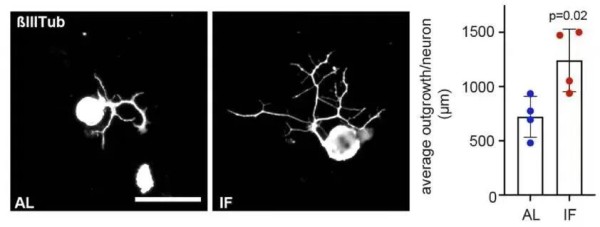

与常规喂养的对照组相比,采用间歇性禁食方案(当天随意进食,隔天禁食)喂养的小鼠,坐骨神经轴突再生速度显著增加,而脊髓背根节神经元轴突生长增加了50%左右。

间歇性禁食组(IF,红色)组与对照组(AL,蓝色)脊髓背根节神经元轴突生长情况区别